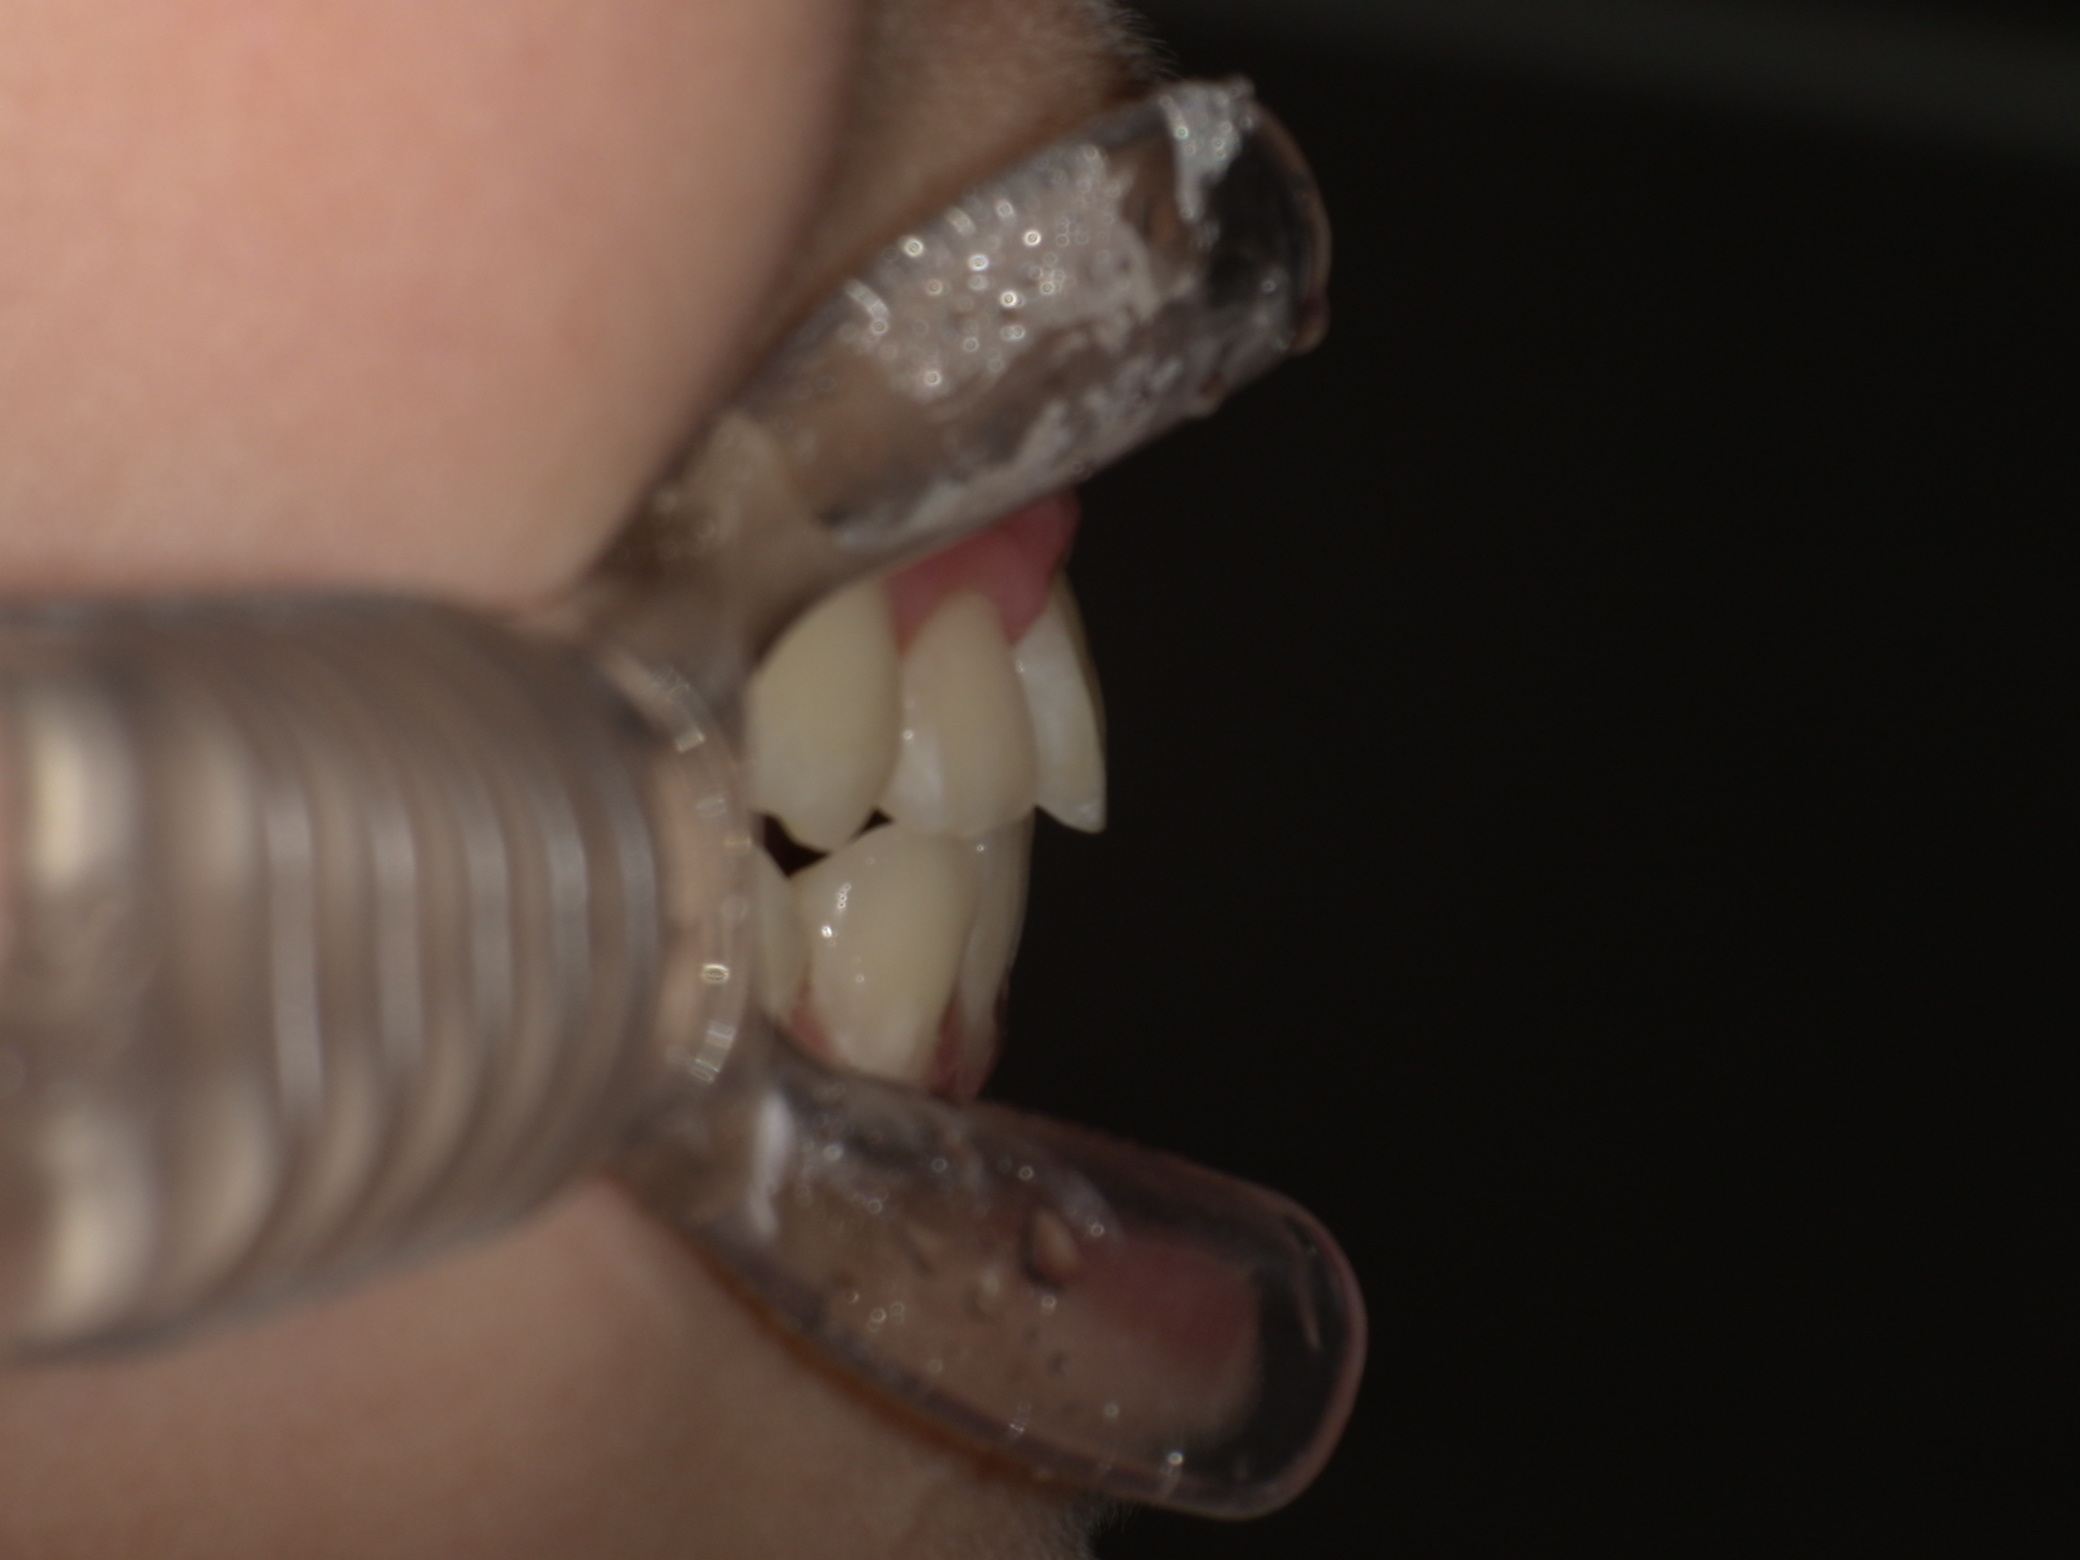

| 年齢・性別 | 男性 |

|---|---|

| 主訴 | 歯並びが気になる |

| 治療期間・回数 | 1年間 |

| 費用 | 330,000円(税込) |